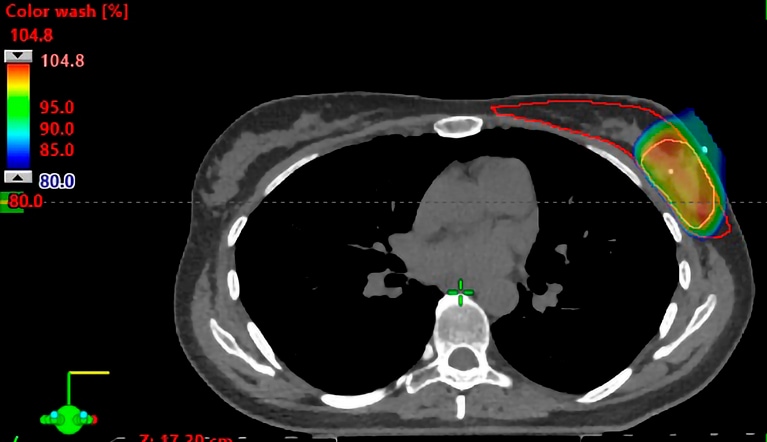

Patients at Mayo Clinic have access to advanced technology and normal tissue-sparing techniques that may not be available at other centers, including proton beam therapy. The Mayo Clinic Proton Beam Therapy Program uses pencil beam scanning, which Mayo Clinic specialists have shown reduces radiation exposure to normal organs in patients with breast cancer. Mayo Clinic investigators have conducted some of the first trials examining whether short-course radiation might also be beneficial in patients with breast cancer undergoing proton therapy.

"One of the challenges is the higher cost of the heavy equipment required to deliver proton therapy, which has limited access," says Dr. Mutter. "By reducing the number of fractions in proton therapy courses, more patients could potentially receive this promising organ-sparing treatment."